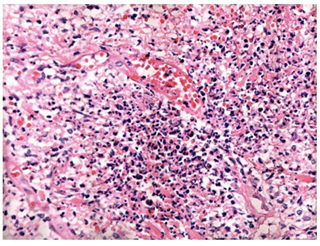

Una semana después se sospechó herpes simple resistente a acyclovir en paciente inmunosuprimida y se solicitaron exámenes paraclínicos para inicio de foscarnet y se tomó biopsia de piel, la cual mostró múltiples neutrófilos invadiendo la dermis y la epidermis sin vasculitis (figuras 1 y 2).

La histología es inespecífica y su principal papel es descartar otros diagnósticos diferenciales como infección, vasculitis, malignidad, etc. En la biopsia de piel se observa infiltrado neutrofílico. La forma vegetativa puede mostrar granulomas con formación de tractos fistulosos y la ampollosa se caracteriza por presentar ampollas subepidérmicas. Siempre se deben enviar muestras para cultivos 1,6,15).